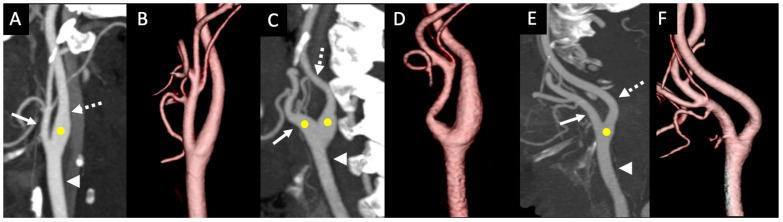

Methods: In this retrospective cross-sectional study, a total of 754 disease-free carotid arteries were examined using computed tomography angiography scans to determine the CS positional variations (such as types I to III) and its morphometry, including the CS diameter and length. Additionally, the association between these parameters and factors such as sex, age, and body mass index were explored using appropriate statistical tests. The inter-rater agreement of the collected dataset was evaluated using Cohen's Kappa.

Results: The CS type I was observed in 87.67% of the cases, and type II and type III were observed at lower frequencies with 9.02% and 3.32%, respectively. There were statistically significant (p < 0.001) differences observed in the mean diameter and length of the sinus between the sex and the type I CS variations. However, there was no significant and strong correlation between the age and BMI factors with sinus length and sinus diameter. The kappa values for inter-rater agreement ranged from 0.77 to 0.99 for all parameters.